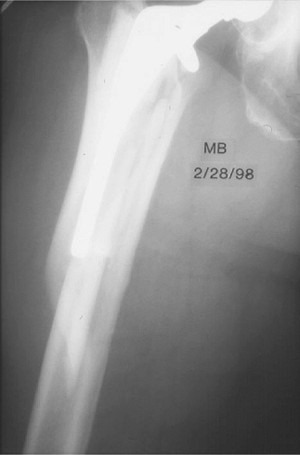

![]() |

|

Figure 45.2. Type II periprosthetic femur fracture originating around the tip of a loose stem.

Figure 45.3. Allograft cortical struts around the proximal femur secured with multiple Luque wires.